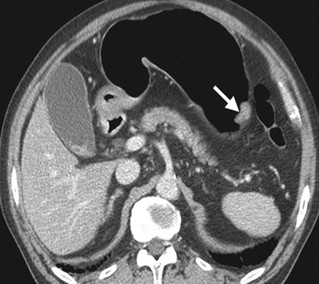

This article has been retracted in accordance with medtigo Journal of Medicine policy (https://journal.medtigo.com/journal-insights/#pub_inte_and_retra). In a post-publication review, concerns were identified regarding permission for use and the copyright status and of certain images used in the article. The author failed to respond to requests for confirmation of permission to use the images in their submission and in our publication. OR The author was unable to provide confirmation of permission to use the images in their submission and in our publication. As a result, the Administrative Editor of the medtigo Journal of Medicine has determined that retraction of this article is necessary to comply with ethical standards and to maintain the integrity of the scientific record.